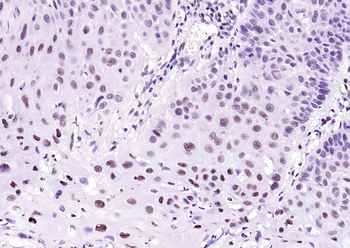

100 μl, 200 μl, 50 μl - LATS2 Rabbit Polyclonal Antibody [orb6306]Featured